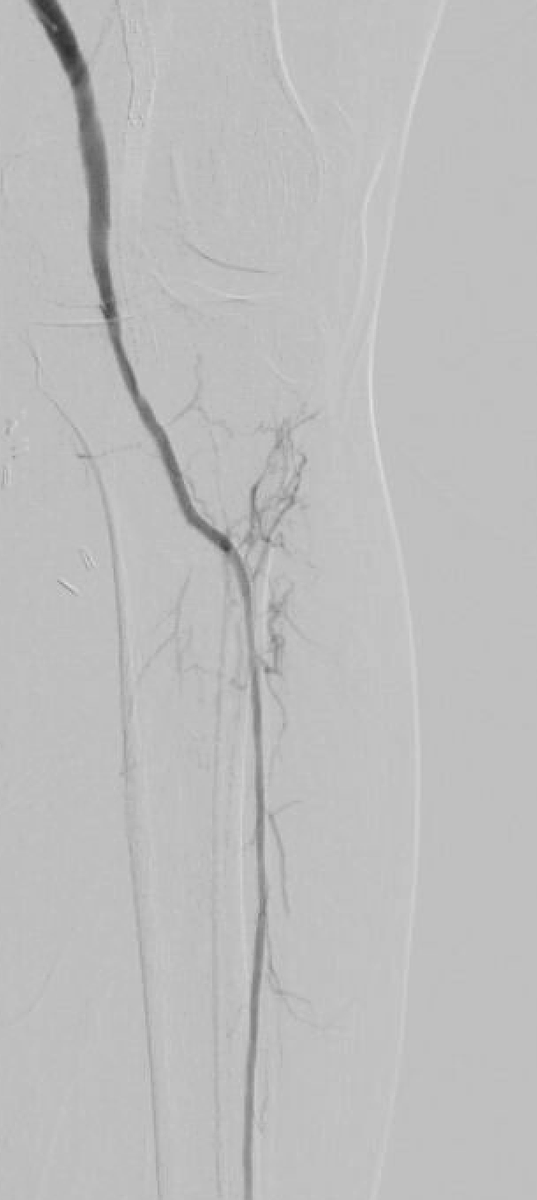

Crossing occluded iliac vein in 43 y/o w venous comp. Doesn’t need to take long w significant symptomatic and wound healing. Crossed w Navi and stiff glide followed by #venovo. @DeanFerreraDO @tlevin @Abd_Alrifai @hendolat @ChristinaR_BDPI @TimHugBD